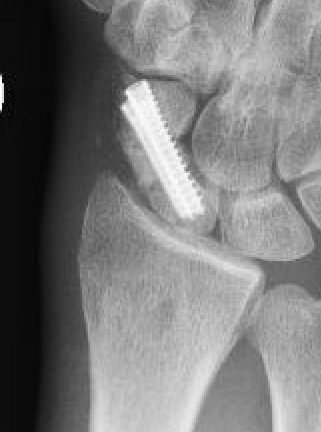

Post scaphoid ORIF

Xray

Fibrous nonunion with minimal displacement and minimal resorption

Nonunion with significant displacement and bone resorption

Proximal pole nonunion with displacement and absorption

Nonunion with increased sclerosis proximal pole consistent with AVN